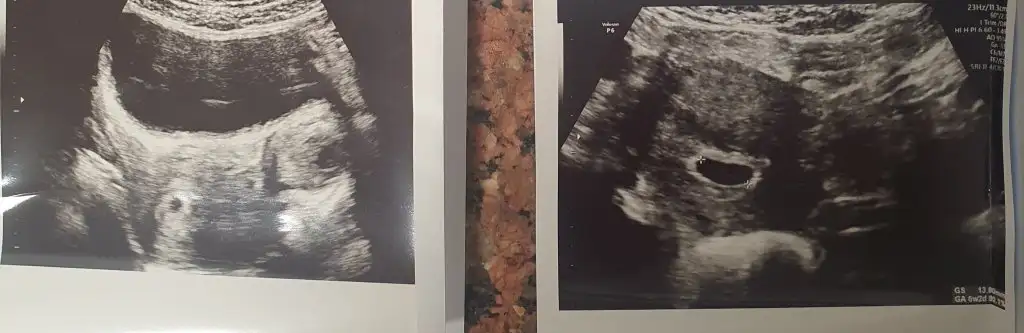

Canım bi tam atar mısın ultrasonuVar teyzesi bak![]()

MaşaallahVar teyzesi bak![]()